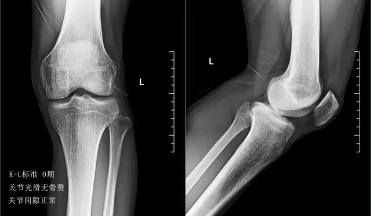

前面已经说到骨关节炎会导致骨赘的形成以及关节间隙的狭窄,所以我们依靠膝关节x片子来初步判断骨关节炎的病情,通常我们采用K_L分期判断病情。

0期的患者:也就是正常的患者,患者不会有任何的症状。